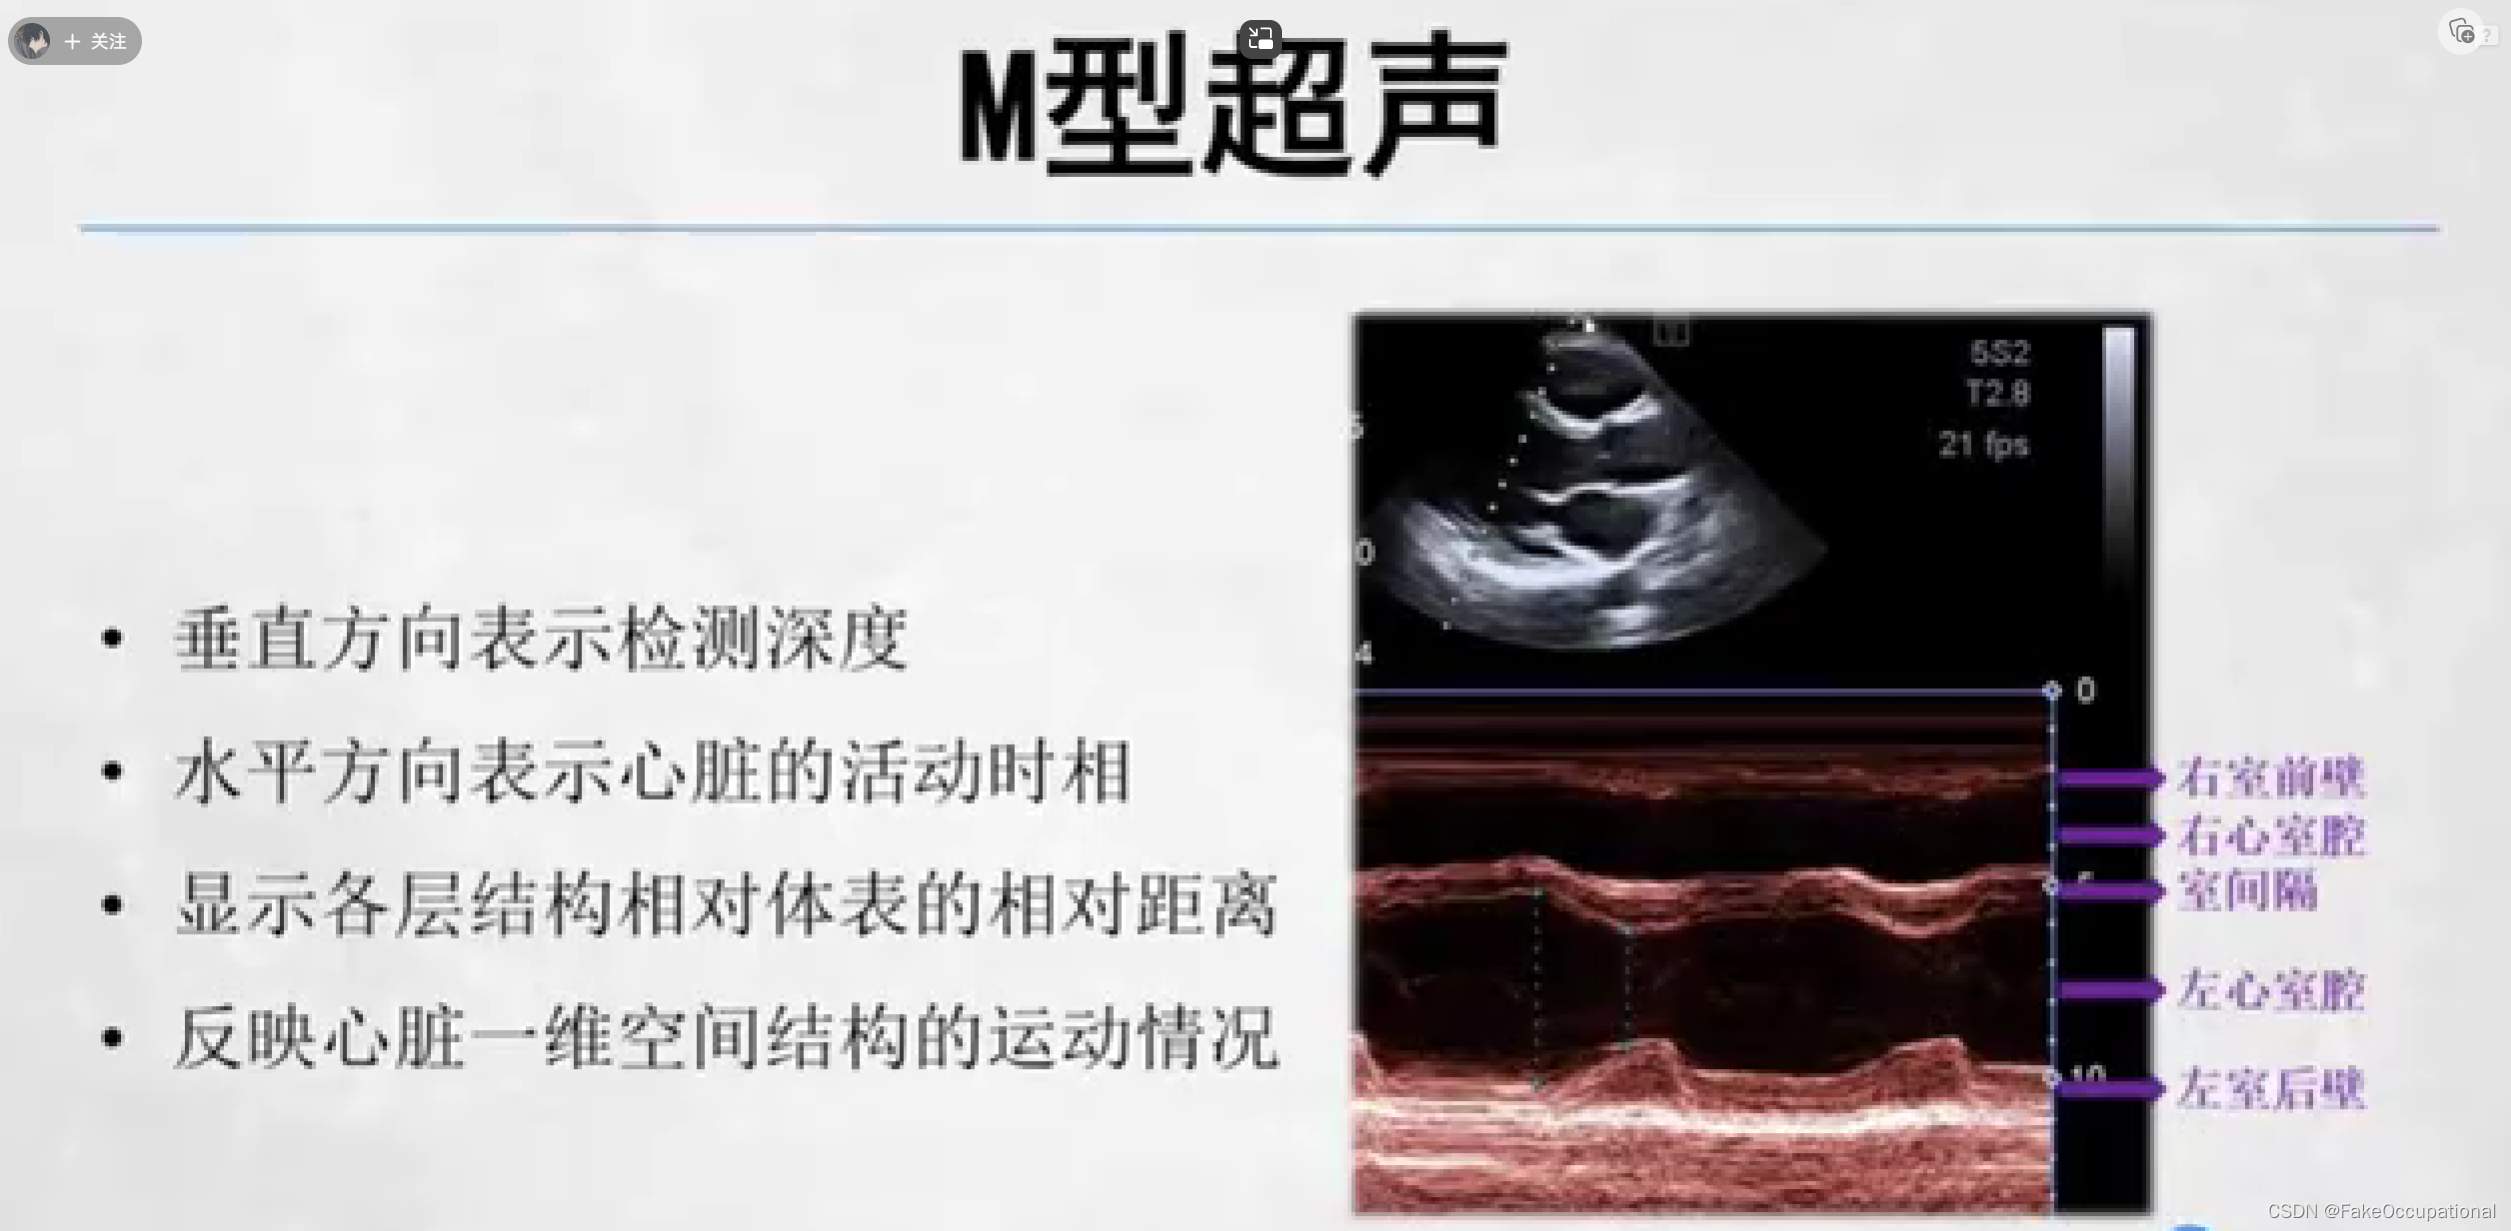

超声成像方法包括A型,B型,M型,D型(频谱多普勒,多普勒血流成像)。

超声心动图检查方法

- 仪器选择常用电子相控阵探头

- 经胸扫查

- 成人2.5-4.0MHz新生儿和儿童5.0-7.0MHZ